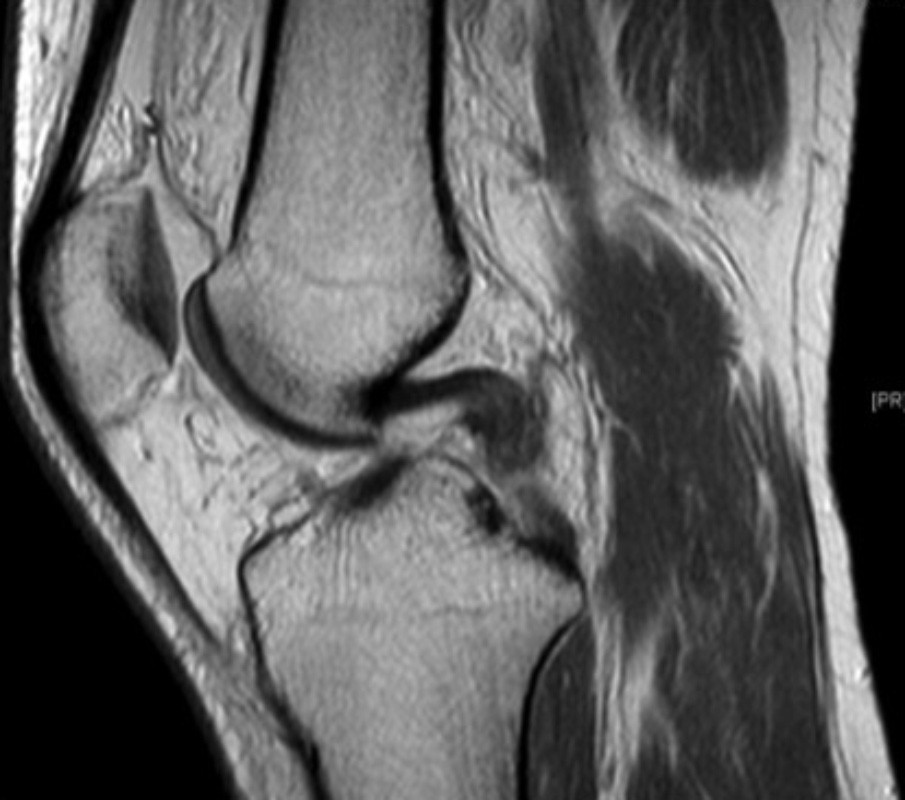

Ist das Kreuzband vollständig abgerissen ist eine Heilung ohne Operation nicht möglich. Um das Kreuzband dennoch zu erhalten kommt die Ligamys® Technik oder „Dynamische Intraligamentäre Stabilisierung“ zum Einsatz. Hierbei wird das abgerissene Kreuzband über eine wenig Millimeter messende Bohrung mit Nähten wieder am Oberschenkelknochen fixiert. Um die Naht in der Zeit der Heilung zu schützen wird eine stabile Kordel als innere Schienung parallel zum Kreuzband gespannt. Diese Kordel wird im Unterschenkelknochen im eigentlichen Ligamys® Implantat verankert. Hier sorgt eine Feder dafür, dass die Kordel über das gesamte Bewegungsausmaß die selbe Spannung behält. Der gesamte Eingriff wird im Rahmen einer Kniegelenksspiegelung also ohne weite Eröffnung des Kniegelenks durchgeführt.